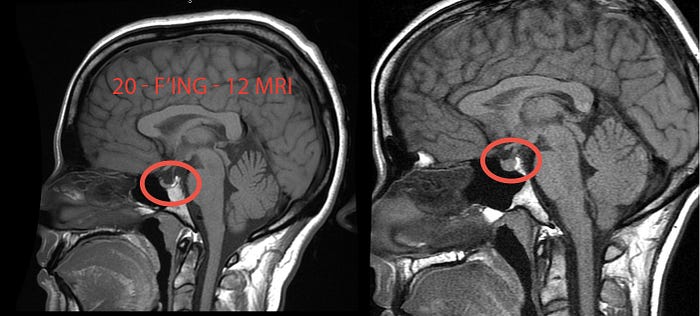

An empty sella is when the sella, a bony space which holds the pituitary gland, appears “empty” (dark/black) on an MRI. This is because the space has been filled with cerebrospinal fluid, flattening the pituitary gland. Most radiologists and neurologists will consider this an “incidental finding,” meaning they believe it’s irrelevant to your symptoms. In my case, as so often happens, the radiologist didn’t even include it in the report. (This is why it is important to always request your original imaging discs, not just the report.)

The neurosurgeon looked at my original 2012 MRI and confirmed that yes, I had an empty sella and that I also had excess cerebrospinal fluid in my optic nerve sheath, a second sign of intracranical hypertension. There is a scene in Unrest, after I come back from my college reunion, where I collapse on the front porch, screaming. I say, “I could feel my head, swelling, pushing out my eyeballs.” Turns out, that is what it feels like to have spinal fluid behind your eyes.

So in March 2018, after all the travel for Unrest had died down, I had an MRV. It confirmed the empty sella and the excess optic nerve sheath fluid he had seen on my 2012 MRI. It also confirmed that I had bilateral transverse venous sinus stenosis (TSS), a narrowing of two veins in the back of the head that drain blood from the brain. TSS is found in 83% of cases of intracranial hypertension (compared to 3% of controls). (It is not known whether TSS is cause or effect, but there is growing evidence that stenting one of the transverse sinus veins can resolve intracranial hypertension.)